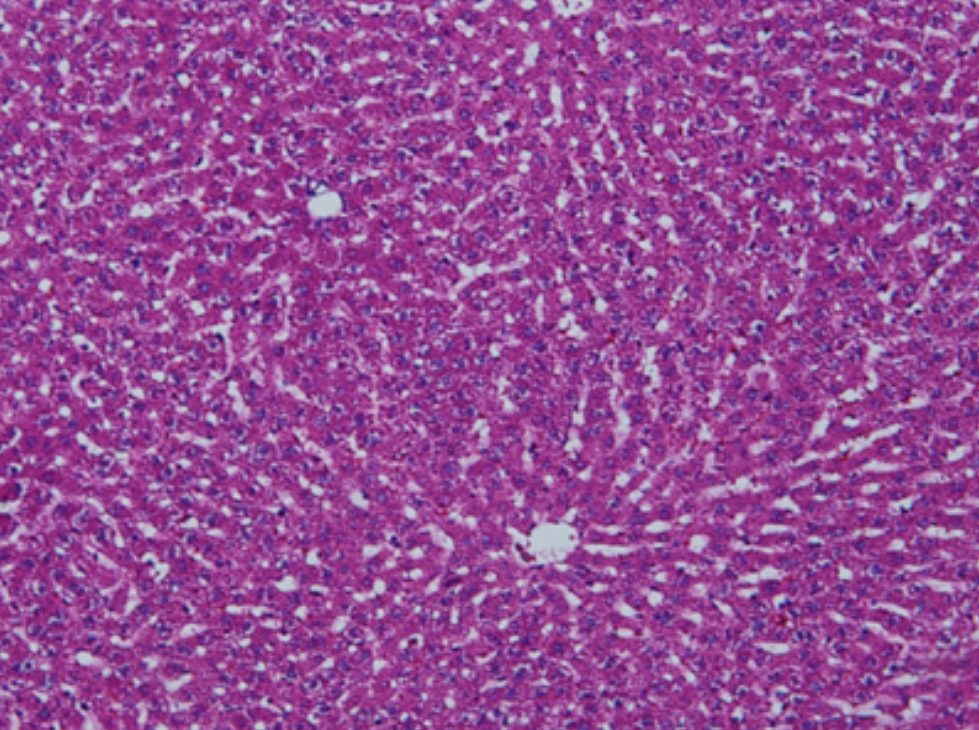

HE染色,全称苏木精-伊红染色法(Hematoxylin and Eosin staining),是最常见的组织切片染色技术之一,用于在显微镜下观察和分析组织或细胞的结构和形态。

虽然HE染色是最常见且最基础的染色技术之一,😭但在实验过程中,很容易出现各种情况导致染色切片质量参差不齐。所以,小编根据以往实验经验,给大家整理归纳出了15个HE染色中的常见问题,还包含问题原因分析以及解决方法哦~

形成原因:切片经梯度乙醇处理后没有完全脱水,导致二甲苯透明、中性树胶封固后残留大量水分。 解决方法:首先移去盖玻片,用二甲苯溶解封固剂如中性树胶,再将切片置入无水乙醇内,待切片重新脱水完全后,用二甲苯透明处理,中性树胶封固。要注意所有用于脱水和透明的液体,在使用一定时间后,应及时更换。 二、细胞核呈红、棕色 形成原因:苏木精染色液过度氧化,切片在苏木精染液染色后返蓝不足。 解决方法:每次染色之前检查苏木精染色液的染色能力,发现苏木精染色液氧化过度应及时更换。此外,切片经苏木精染色后,要给切片以足够的蓝化时间,蓝化过程可用流水、温水、弱碱性溶液(如稀氨水或0.2%碳酸氢钠)等处理。 三、切片在脱蜡后出现大片白色斑点 形成原因:由于烤(烘)片温度太低,切片上的组织蜡膜在脱蜡前没有充分烤(烘)融化。或是因为切片在二甲苯液中停留时间不足,或二甲苯使用过久,造成的脱蜡不彻底。 解决方法:若是由于切片烤(烘)温度低所致,可以先用二甲苯去除切片上的封固胶,然后重新用二甲苯脱去切片上的石蜡,再进行后续染色。若是由于切片在脱蜡的二甲苯中停留时间不足或脱蜡二甲苯使用过久浓度不足所致,则需将切片退回到二甲苯中,停留较长时间,或更换二甲苯液体重新脱蜡,再入乙醇重新脱二甲苯,入0.5%盐酸水溶液褪色后,重新HE染色。 四、细胞核苍白暗淡,即苏木精染色太淡 形成原因:切片在苏木精染色液停留时间太短;苏木精染色液过度氧化,失去染色能力,不能再继续使用;分化步骤处理时间过长;固定不及时。此外值得注意的是,若骨组织细胞核暗淡,大多是脱钙过度造成的。 解决方法:切片重新染色。如果组织在酸性固定液(如Zenker、Bouin)或非中性缓冲甲醛液固定时间过长,细胞核染色能力将减弱,需增加其在苏木精染色液的时间,或用一些方法增加组织的嗜碱性,以改善细胞核的着色。例如,上述组织玻片可以使用Weigert铁苏木精染色液。如果组织是用Zenker液固定的,可将切片脱蜡后放在5%碳酸氢钠溶液3~4h,流水冲洗5min后染色。如果组织是用Bouin液固定的,可将切片脱蜡后放在5%碳酸锂1h,流水冲洗10min后染色。 五、细胞核过染,苏木精染液占据了细胞质 形成原因:玻片在苏木精染色液停留时间过长,或是切片太厚、分化步骤时间太短。 解决方法:如果不是因为切片太厚(用显微镜仔细上下微调,只有一二层细胞核层次),就需将切片进行脱色、漂白、重新染色,适当调整染色和分化时间。但如果确定是由于切片太厚导致的细胞核过染,则需要重新切片。 六、伊红着色淡 形成原因:可能是伊红染液pH值大于5,也可能是蓝化液残留过多,切片太薄,或是切片经伊红染色后在乙醇脱水时间过长。 解决方法:检查伊红染液pH值,必要的话,用乙酸将其调节在4.6~5.0之间,从而使伊红染色色彩艳丽。此外,确保每次蓝化步骤完成后,使用的弱碱性溶液被充分洗去,玻片上没有残留的弱碱性溶液。最后,检查切片的厚度,且脱水时不要让切片在低浓度乙醇中停留时间过长,因为含水多的低浓度乙醇会将切片伊红的颜色分化掉。 七、细胞质过染、分色不足 形成原因:伊红染色液浓度太高,特别是存在焰红燃料、四溴四氯荧光素钠。切片在伊红染色时间过长,或是切片在伊红染色后经乙醇脱水步骤时时间太短,而使乙醇分化伊红的作用不能产生,都能够使细胞质过染。 解决方法:适当稀释伊红染色液,减少伊红染色时间,或使切片在乙醇脱水等步骤时,停留时间相对均匀。同样,也要检查切片的厚度是否合适。 八、切片中出现蓝黑色沉淀物 形成原因:苏木精染色液中的金属膜黏附在玻片上。 解决方法:染色前仔细过滤苏木精染色液,建议使用半氧化苏木精染色液,如Gill苏木精染色液,可以避免过多的金属膜产生。 九、光镜下切片某些区域难以聚焦 形成原因:盖玻片上可能有封固切片的封固剂。 解决方法:移去盖玻片,重新用干净的盖玻片封片。检查切片封片方法,是人工手工封法,还是机器自动封法,如有问题及时调整。 十、封固剂从盖玻片与载玻片之间的缝隙回缩 形成原因:盖玻片弯曲或不平整,或是封固剂含二甲苯过多,稀释过度。 解决方法:移去盖玻片,重新找一张盖玻片,用干净的封固剂封片。如用手工封片法,保证在封固结束时,封固剂容器盖子为紧闭状态。且尽量使用小的容器盛装封固剂,一旦封固剂太黏稠,就可以选择废弃。 十一、细胞核呈灰蓝状态 形成原因:可能由于组织处理温度过高、过热,在液体石蜡中停留的时间过长。或是固定时间太短后,直接在高浓度的乙醇中进行了脱水处理。 解决方法:理论上来说,仅在组织浸蜡步骤才进行加热,组织不能在热蜡液中停留太久。如果由于某些原因不能进行下一步包埋处理,可将组织连同塑料包埋盒一并放置在室温空气中,冷却凝固,以备包埋。待需要包埋时再重新加温直至石蜡融化即可。组织在处理前必须确保固定良好,脱水最好能从低浓度的乙醇开始。 十二、类色素的点状结晶和黑色光滑细胞核 形成原因:这种裸核改变是因为切片封片前放置在空气中的时间太长,以至于二甲苯挥发,切片干燥。 解决方法:移去组织切片上的盖玻片和封固剂,重新处理。将切片水洗数分钟,然后重新脱水、透明、封固。封片过程中要保持组织切片的轻度湿润,尽量不要让其干燥。 十三、染色过淡或过浓 解决方法:如果染色过淡,可以增加染色剂的浓度、延长染色时间或更换新鲜的染色剂;如果染色过浓,则应减少染色剂的浓度或缩短染色时间。 十四、切片出现叠加褶皱 形成原因:新购买的玻片洁净度不够、用镊子撑开切片时操作不够熟练未能平整伸展,或玻片表面有油脂,切片粘贴不牢。另外,烤片时间不足、烤片温度过低或切片过厚造成切片脱落,都会造成重叠或有皱褶的情况。 解决方法:新购买的玻片最好能用硫酸清洁液浸泡一晚,然后流水冲洗干净。在适宜的温度下烤片时间宁长勿短,保证有充足的烤片时间和温度。另外,切片刀要锋利,才能切出厚薄适宜的切片,保证切片不会因为过厚而脱落。 十五、组织残缺不全或有刮划痕迹 形成原因:组织残缺不全是由于切片时修整蜡块时深度不够、组织没有全部暴露于切面。切片的刮划痕迹是由于切片刀的刀锋有缺口、包埋的组织有异物,或是钙化组织、骨组织及包埋石蜡有沙粒造成的。 解决方法:修整蜡块时保证组织块全部暴露于切面,切片时保证切片刀的锋利没刀口。同时在组织取材时去除手术异物和钙化组织。最后,骨组织要完全脱钙,这样可以保证切片的完整和平整美观。 *注:由于实验中导致结果出现误差的原因多种多样,以上内容仅供参考,具体根据实际情况进行判断。